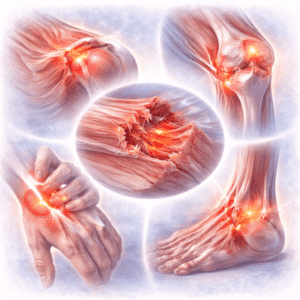

Guaranteed Relief for Back Muscle Joint Pain

Back muscle joint pain is a quiet thief, taking your energy, comfort,…

Back, Muscle & Joint Pain: Causes, Types, Treatments & FAQs

Back, muscle, and joint pain is more than just an inconvenience. It…